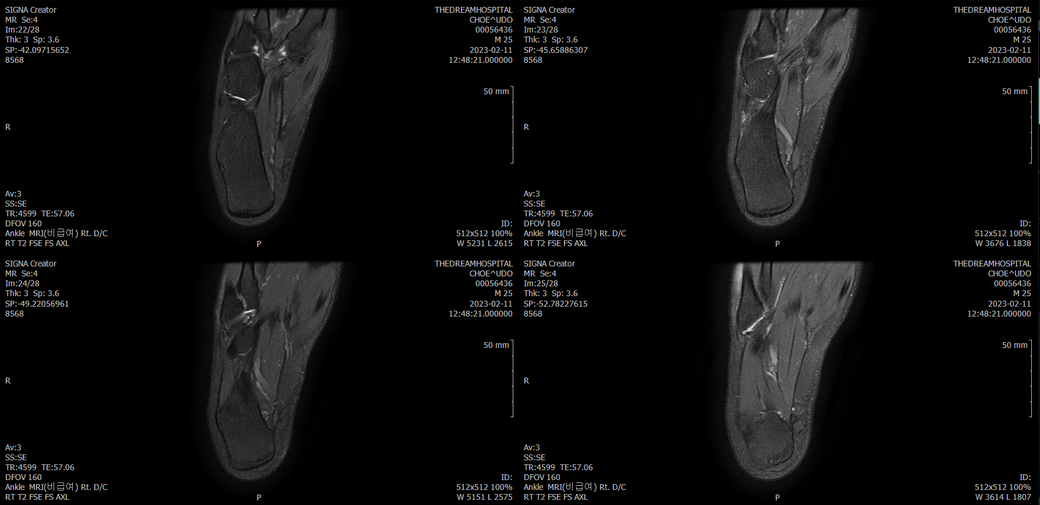

오른발목 mri 전체사진입니다. 제가 병원을 갈수없는상황인지라.... 봐주시면 감사하겠습니다.

엑스레이에서는 문제가 없다고 하여 오른발목 mri촬영했습니다.